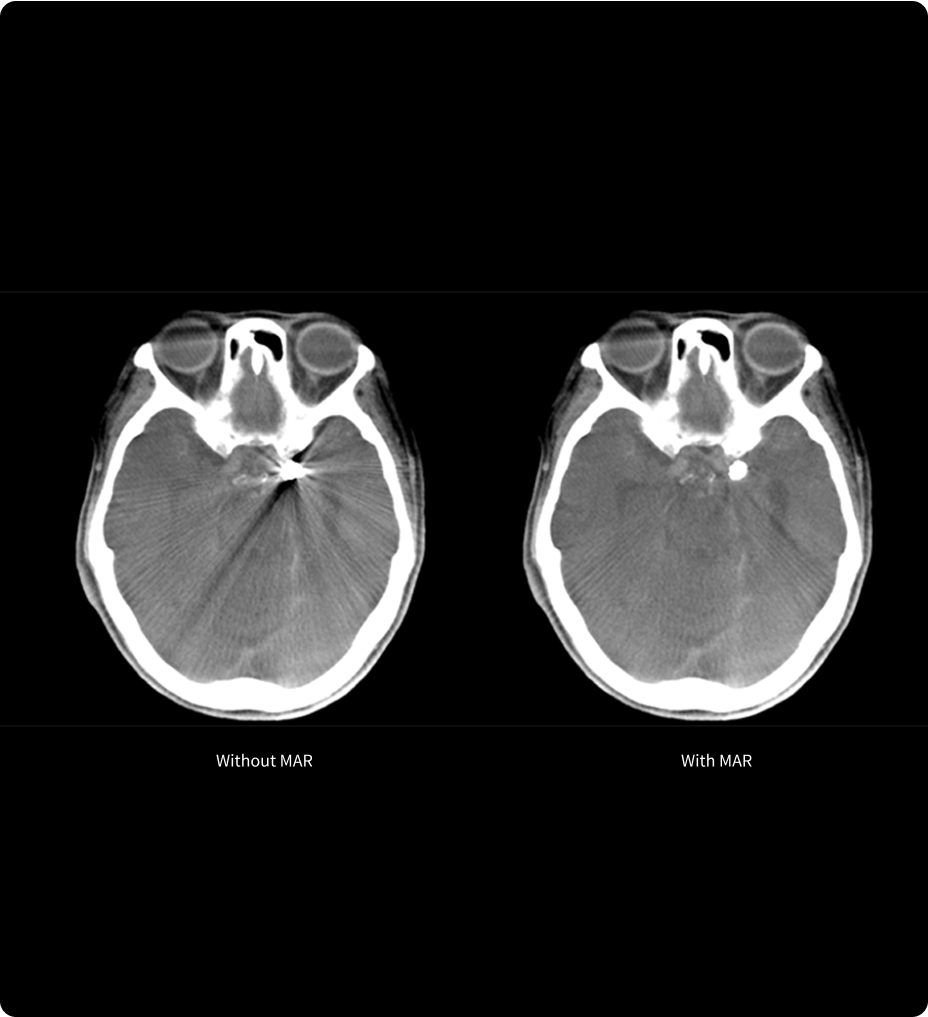

• SNC (IRM crânienne et rachidienne et études de perfusion)